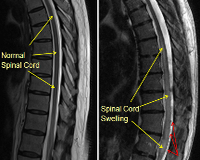

Посттравматический отек вызывает ишемию спинного мозга, которая повреждает миелиновые оболочки нервов. Впоследствии образуется специфический глиоз - замена мертвых нейронов нейроглиальными клетками, что сопровождается нарушением функций позвоночника. Эти изменения видны на МРТ в виде миомаляции: в первые полгода состояние может быть частично обратимым, затем фиксируется стойкий неврологический дефицит.

• МРТ спинного мозга. Обследование считается наиболее информативным для изучения строения органа, выявления местного поражения нервной ткани, симптомов основного заболевания, вызвавшего отек. Если МРТ недоступна, проводится КТ спинного мозга.